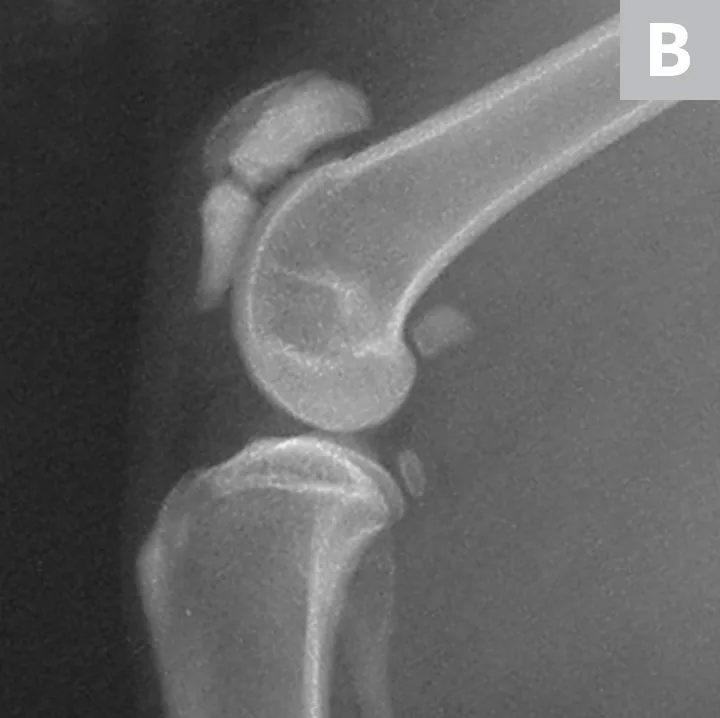

The patient received buprenorphine (15 µg/kg IV) for analgesia, followed by an induction with alfaxalone (0.5 mg/kg IV) and general anesthesia with isoflurane to facilitate dental and orthopedic radiography. Dental radiographs revealed persistent deciduous teeth and impacted permanent teeth. Lateral and craniocaudal pelvic limb radiographs revealed a displaced left patellar fracture and a nondisplaced right patellar fracture (Figure 2).

Lateral radiographs of the left (A) and right (B) stifles show a complete, displaced left patellar fracture and a nondisplaced right patellar fracture, respectively.